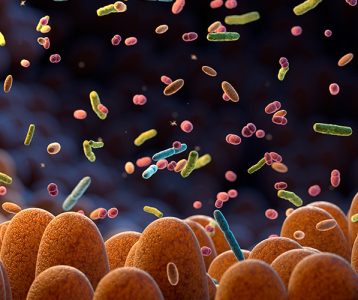

Para o presidente do Comitê Científico do Yakult International Symposia on Beneficial Microbes – Fundamental Science and Innovative Applications, Prof. Dr. Svetoslav Dimitrov Todorov, a ciência dos probióticos, assim como a compreensão do papel e da utilização desses microrganismos, vem sendo amadurecida. “Probióticos passaram de ‘simples’ produtos fermentados que melhoram o estado imunológico ou desequilíbrios gastrointestinais para ‘sofisticadas’ formulações farmacêuticas sob medida para otimizar várias funções fisiológicas”, ressalta.

De acordo com o professor, que é docente e pesquisador do Departamento de Alimentos e Nutrição Experimental da Faculdade de Ciências Farmacêuticas da Universidade de São Paulo, cabe aos cientistas reconhecerem que ainda estão na fase nascente da ciência dos probióticos, apesar de quase um século de exploração em suas aplicações. “Entretanto, hoje estamos mais perto de realizar o sonho de Hipócrates de que um dia nosso alimento se tornará Medicina e nossa Medicina se tornará alimento”, acrescenta.

- Probióticos e saúde intestinal

- Mecanismos de ação dos probióticos